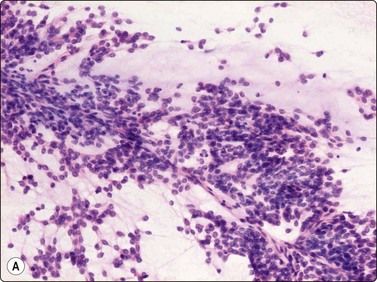

The pseudosarcomatous lesions are an important target for needling in this histogenetic group of tumors/lesions. Nodular fasciitis is among the commonest and the most frequently needled. Dahl and Åkerman reported 13 cases with cytology 1981;12 at present, our material comprises more than 70 cases, all with remarkably similar cytomorphology. In more recent investigations of the cytological features of nodular fasciitis, the results are similar to those of Åkerman and Dahl.13,14 The most important feature is the pleomorphism of the proliferating fibroblasts/myofibroblasts. Nuclei are predominantly spindly, but a proportion of cells have plump, ovoid or kidney-shaped nuclei. Bi-and/or multinucleated forms are always present and, if looked for carefully, ganglion cell-like binucleate cells with triangular shape and eccentrically placed nuclei are found (Fig. 15.1). A high cell content, nuclear pleomorphism, prominent nucleoli and the presence of mitoses may suggest malignancy, but the pale, bland nuclear chromatin is a clear indication of the benign nature of the lesion (Fig. 15.2). The correct diagnosis depends on the clinical presentation and the anatomical site (a rapidly, often tender subcutaneous nodule most frequently appearing in the upper extremity, trunk, head and neck) combined with such cytologic features as a myxoid background, actively proliferating fibroblasts/myofibroblasts and the presence of inflammatory cells.

Fig. 15.1 Nodular fasciitis

Proliferating fibroblasts embedded in a myxoid background; note binucleate cell with abundant cytoplasm and eccentric nuclei (ganglion cell-like) (MGG, HP).